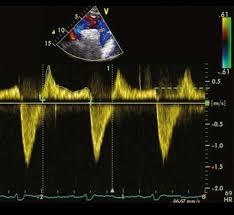

Flying w sign

What diagnosis is consistent with this spectral Doppler?

What sign is seen?